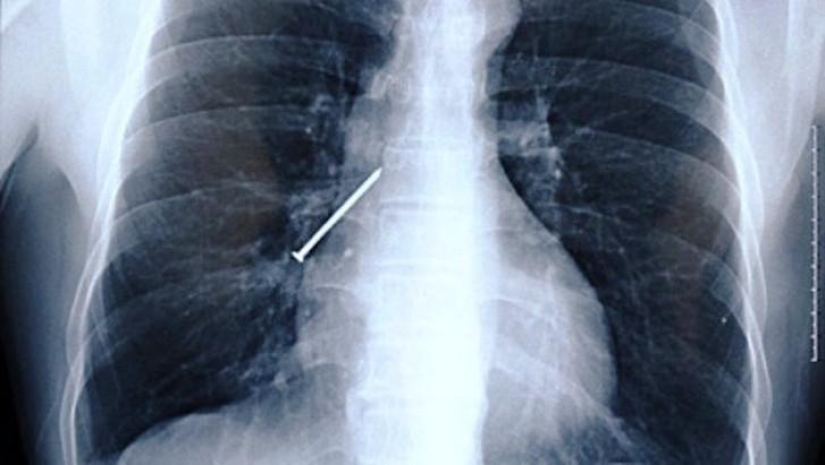

10. The nail.